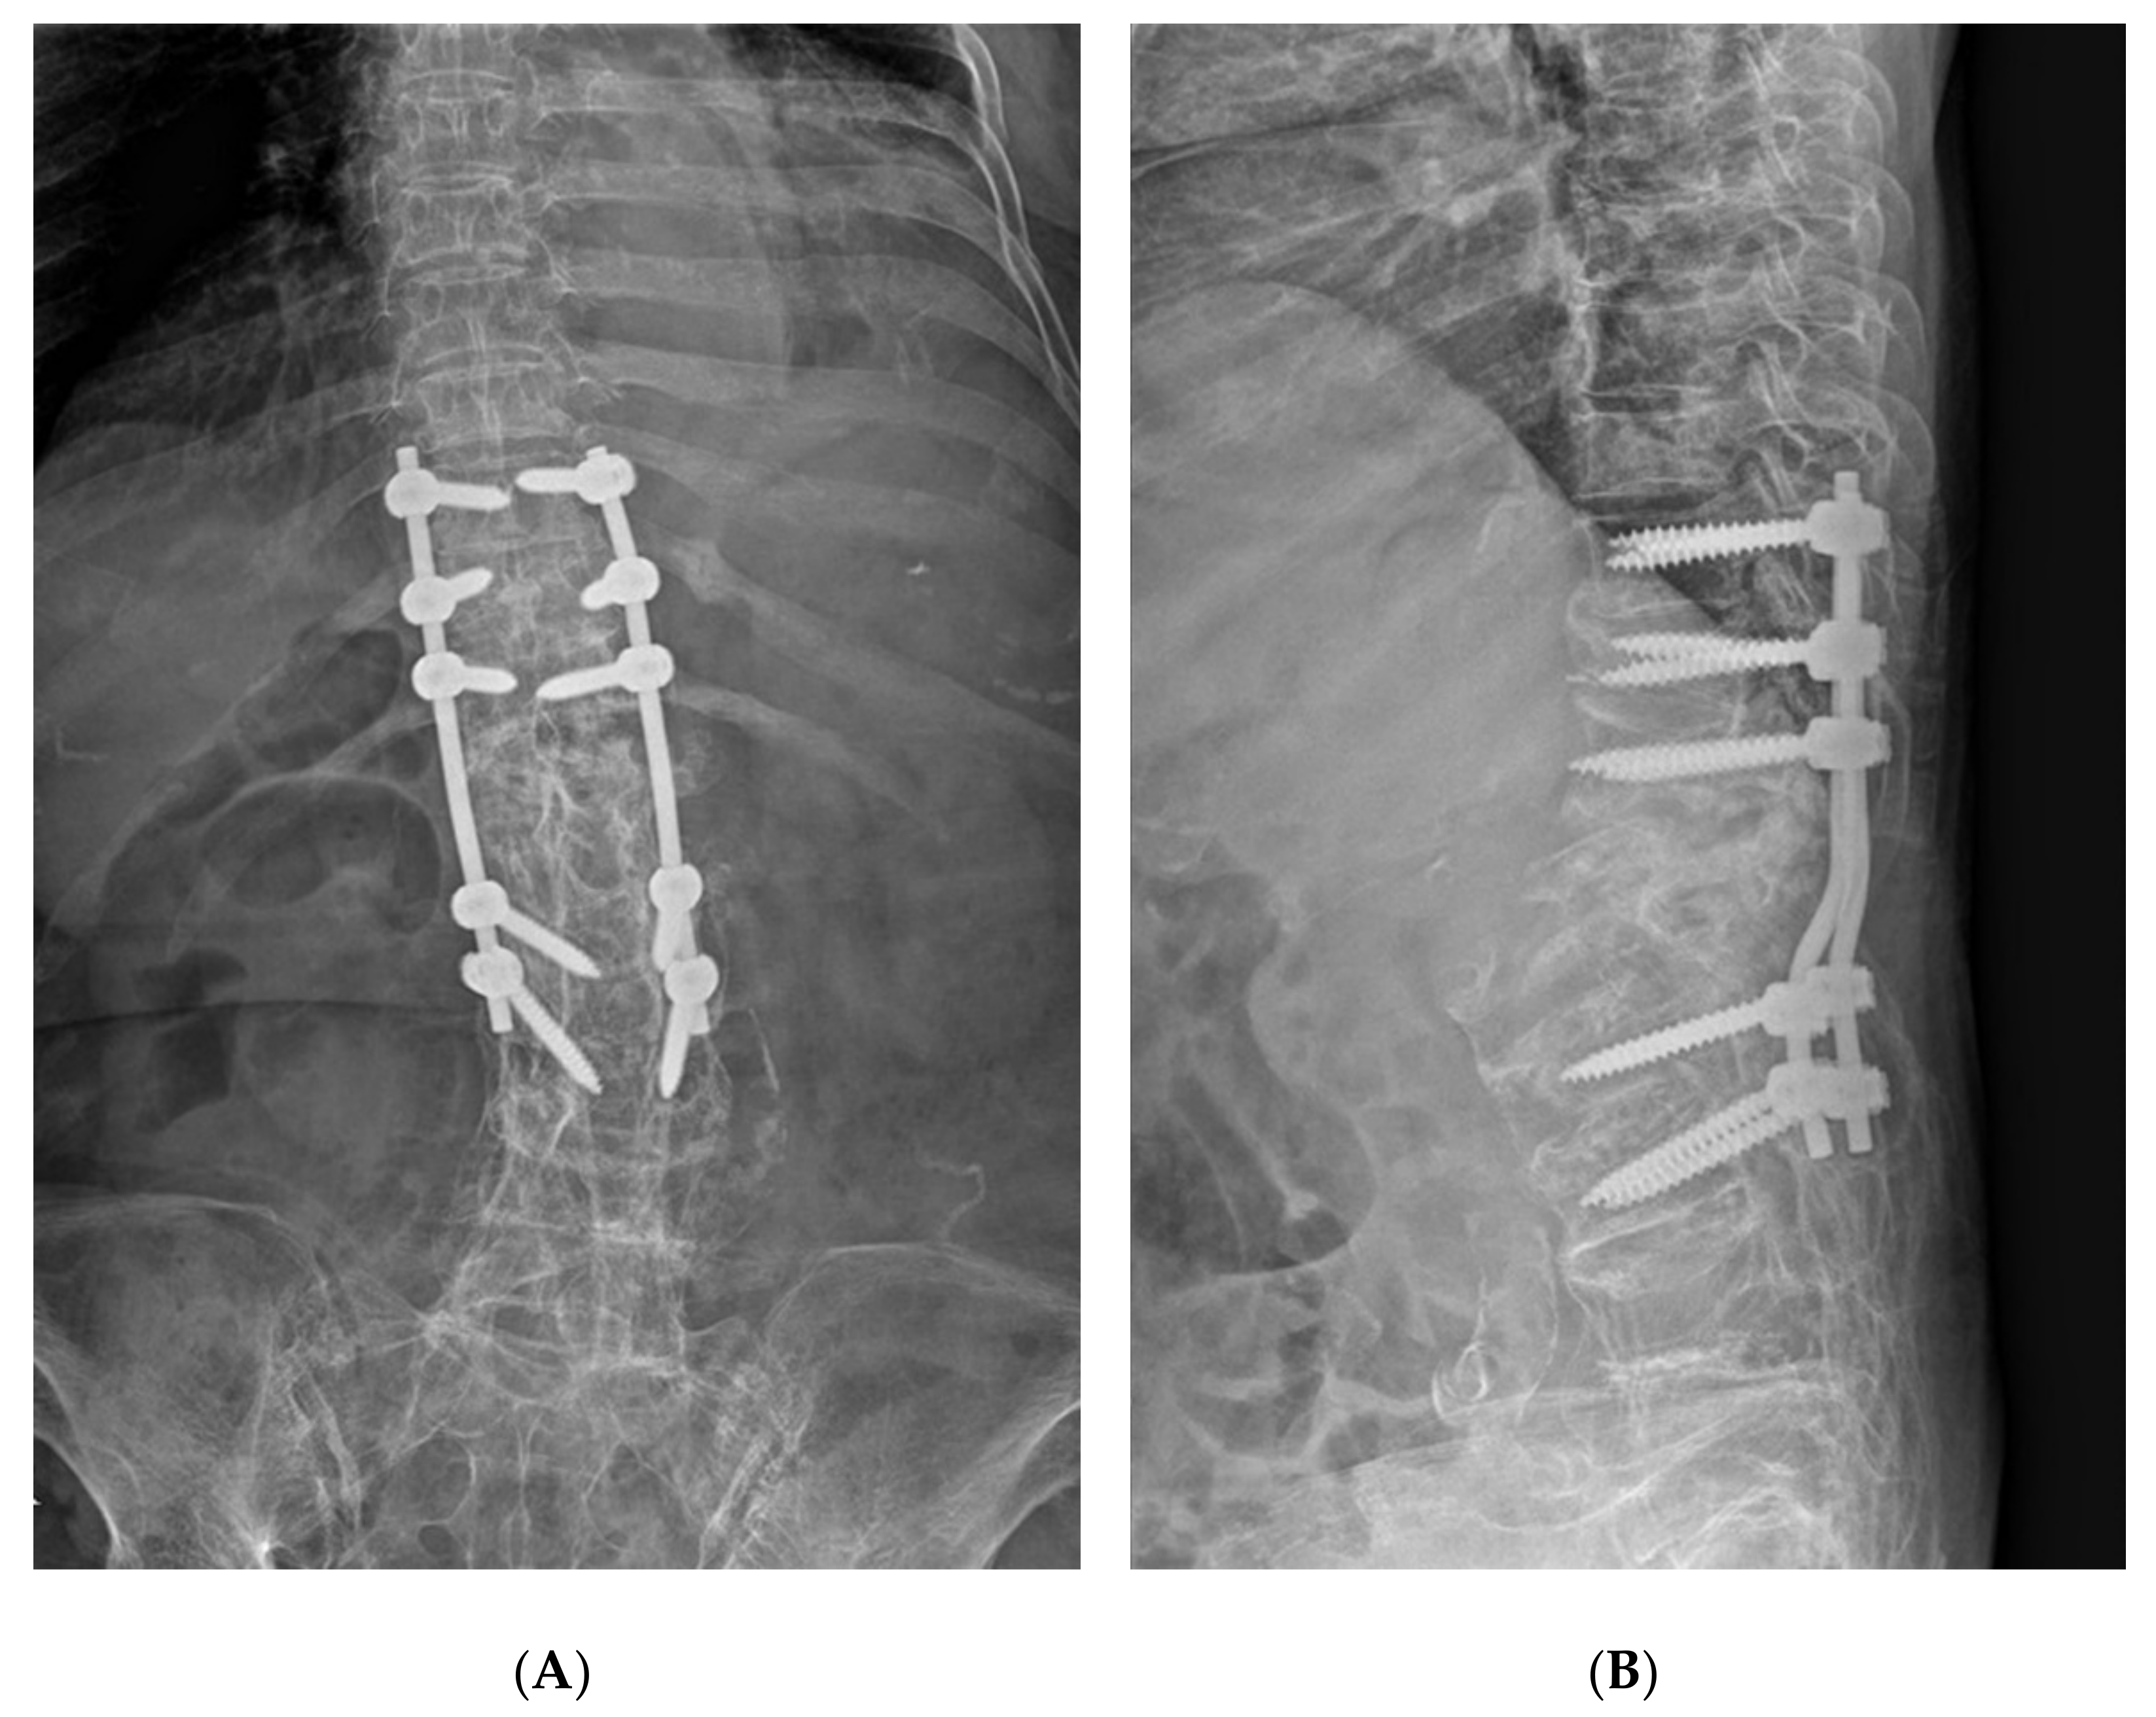

2. Case Presentation